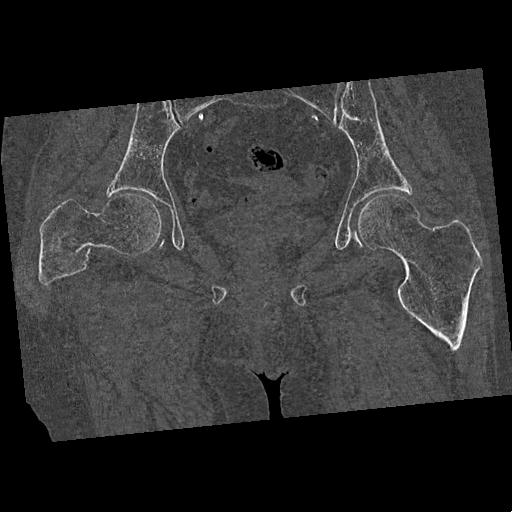

100703 1/27 両股正面+軸 1/29 両股正面+軸 94歳女性 パンソンロン